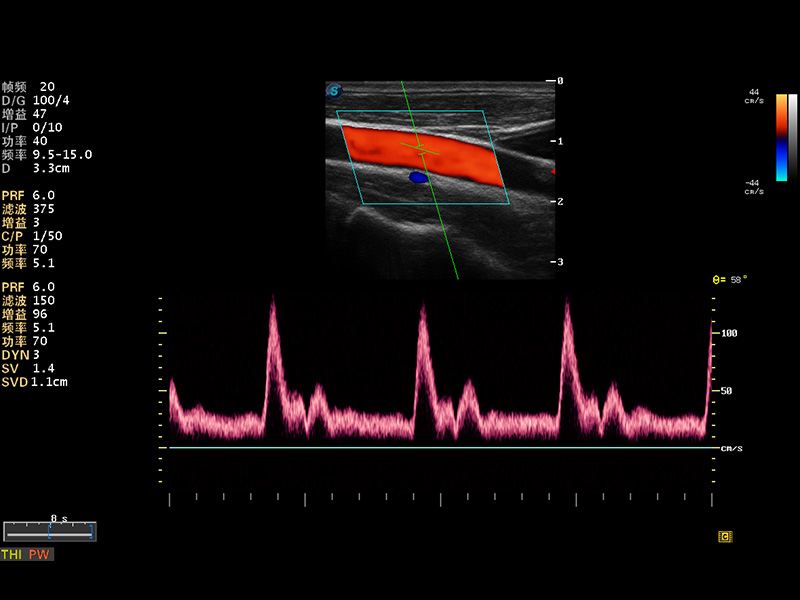

S8 EXP便携式彩色多普勒超声诊断仪是开立医疗研发的高端全身应用型便携彩超。高通道的VIS平台融合可视化(Visual)、智能化(Intelligent)和人性化(Smart)的特点,配以开立医疗自主研发生产的探头大家族,使您能够快速、准确的获得病人信息,提高工作效率的同时减轻疲劳。

成像技术

多波束形成器